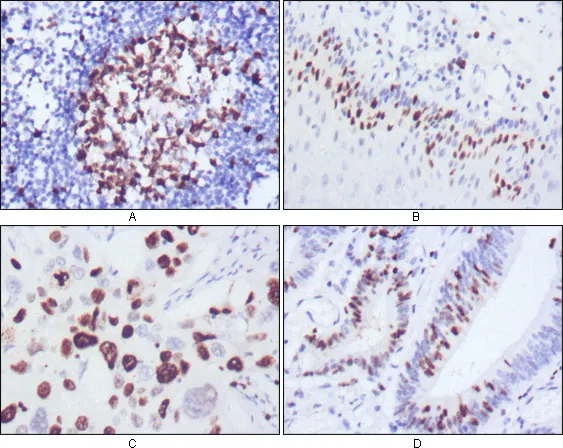

Ki67 (10B6) Mouse Monoclonal Antibody

Cat: AMM00719

Size1:50μl Price1:$150

Size2:100μl Price2:$280

Size3:500μl Price3:$1200